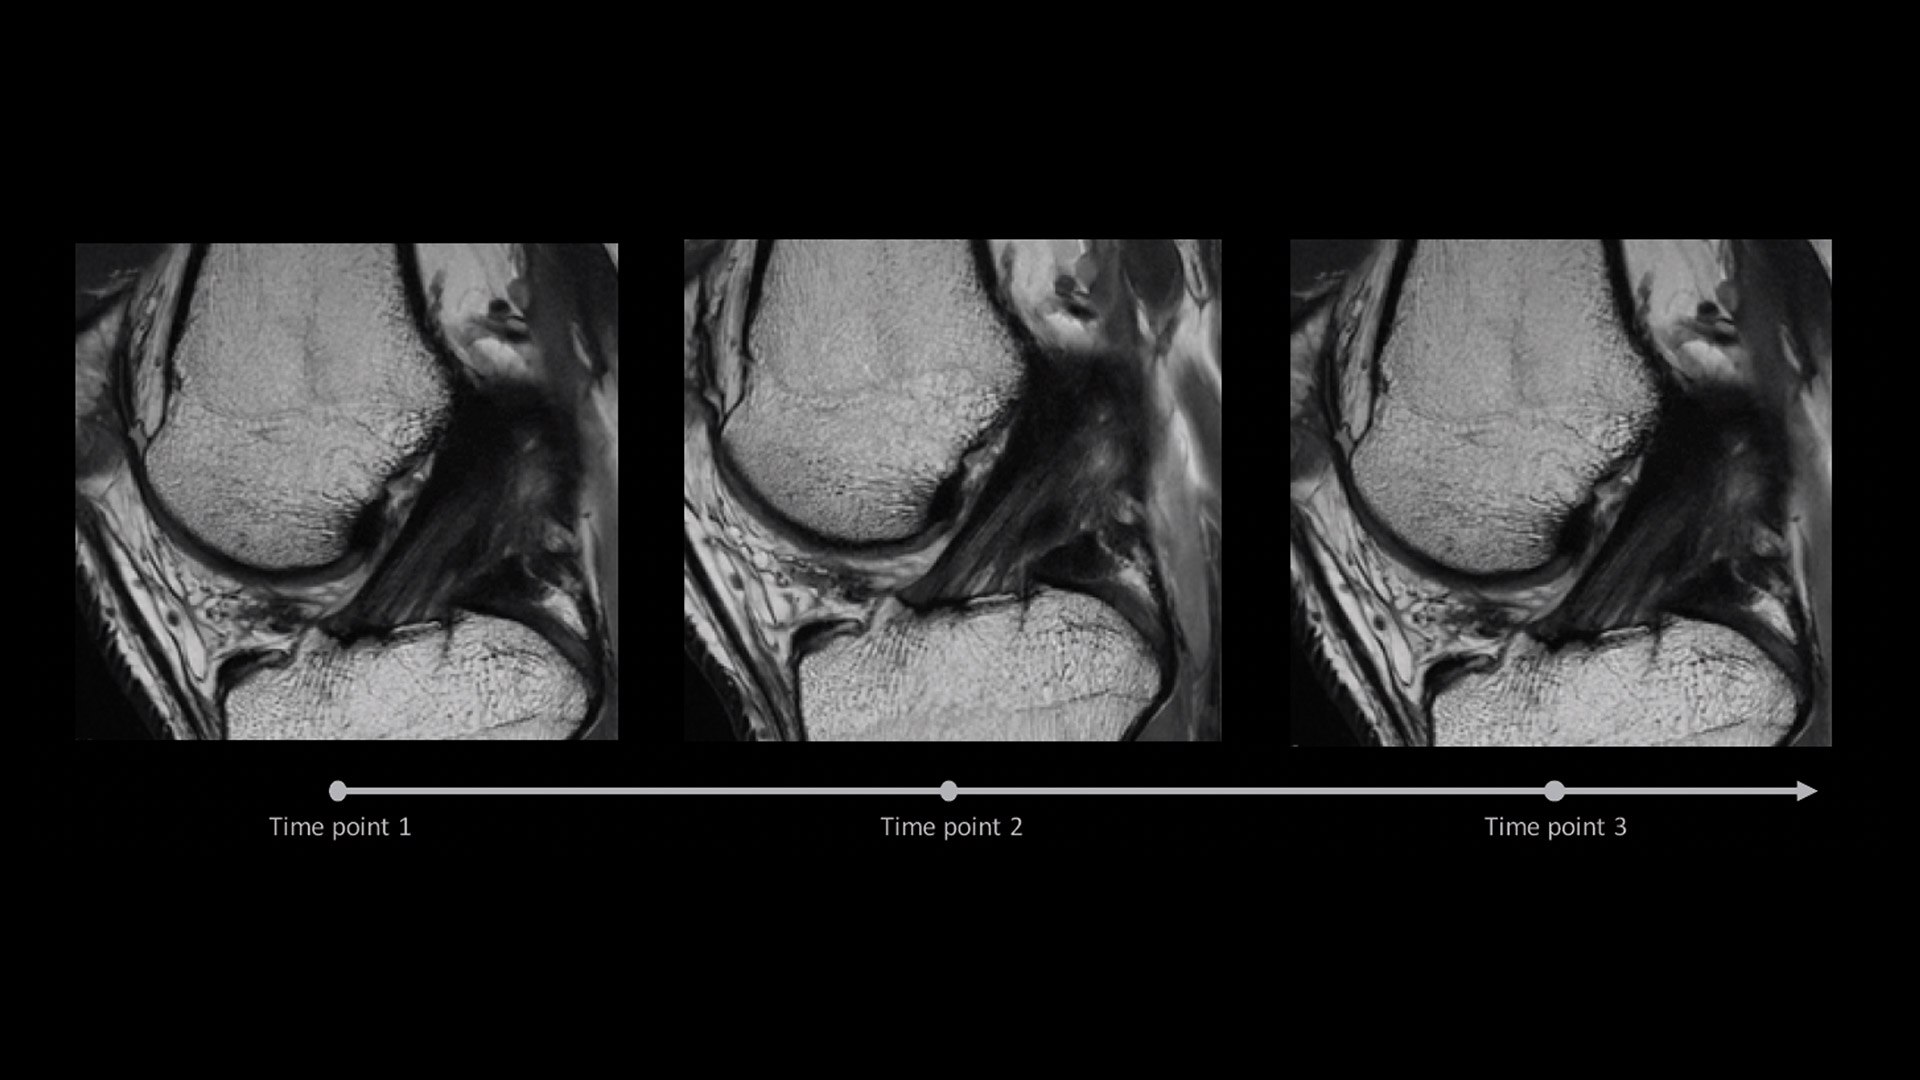

AIR x™ automatically detects patient anatomy and prescribes MRI slices for routine and challenging neurological and knee exams, delivering consistent and quantifiable results.

Deliver consistent MRI slice placements across multiple clinical time points, with a deep-learning algorithm that provides efficiency and time savings.